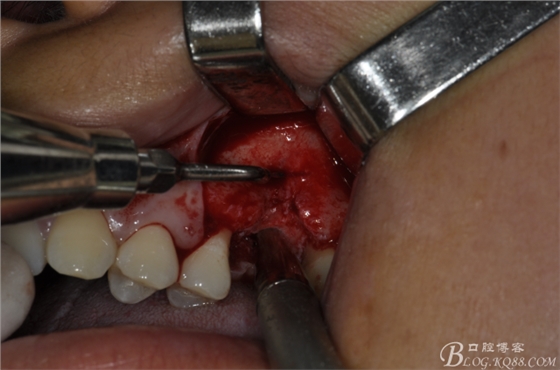

術(shù)中照片。

超聲骨刀切開(kāi)骨外板